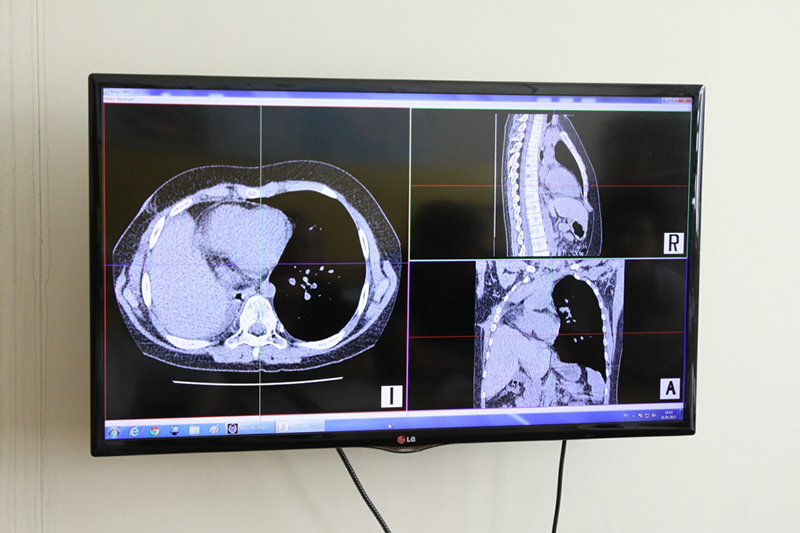

«Центр видеоконсультирования работает уже около года. Результаты томографии наши фтизиатры получают с любой территории края по Интернету и помогают коллегам в постановке диагноза и выработке тактики лечения», – сообщил главврач.